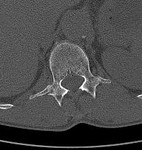

[画像診断]仙骨脆弱性骨折について【初期研修医と学ぶ】 2010-08-20